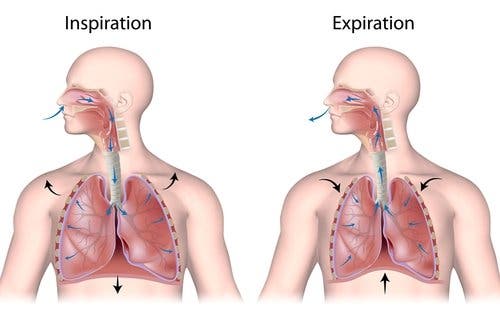

Las enfermedades respiratorias afectan a las vías nasales, los bronquios y los pulmones. Comprenden desde infecciones agudas como la neumonía, la bronquitis y el catarro común. También se incluyen las enfermedades crónicas como el asma y la enfermedad crónica obstructiva (EPOC)

Los síntomas más comunes que pueden aparecer en las enfermedades respiratorias son la tos, la falta de aire y las secreciones respiratorias.

Estos síntomas, se presentan con intensidad variable de una persona a otra. Además, los síntomas también varían en función de la enfermedad en cuestión, el grado de severidad y el tiempo de evolución.

Las enfermedades respiratorias afectan a las vías nasales, los bronquios y los pulmones. Comprenden desde infecciones agudas como la neumonía, la bronquitis y el catarro común. También se incluyen las enfermedades crónicas como el asma y la enfermedad crónica obstructiva (EPOC)

Los síntomas más comunes que pueden aparecer en las enfermedades respiratorias son la tos, la falta de aire y las secreciones respiratorias.

Estos síntomas, se presentan con intensidad variable de una persona a otra. Además, los síntomas también varían en función de la enfermedad en cuestión, el grado de severidad y el tiempo de evolución.